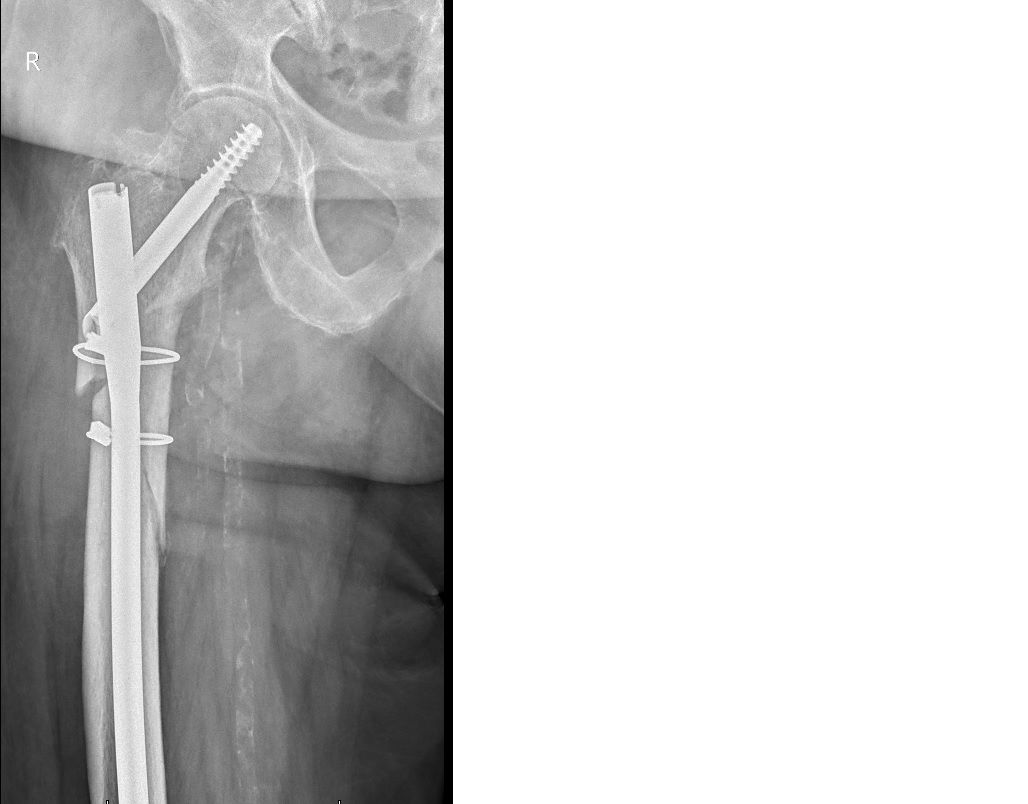

Złamania kości. Skręcenia i zwichnięcia stawów.

Choroba zwyrodnieniowe bioder i kolan - endoprotezoplastyki.

Zdjęcia i filmy